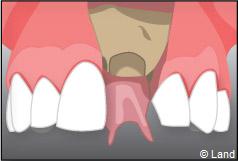

Exemple d’un implant unitaire pour remplacer une dent antérieure manquante.

– le remplacement d’une dent unitaire. Grâce à ce procédé, il n’y a pas de mutilation des dents voisines.